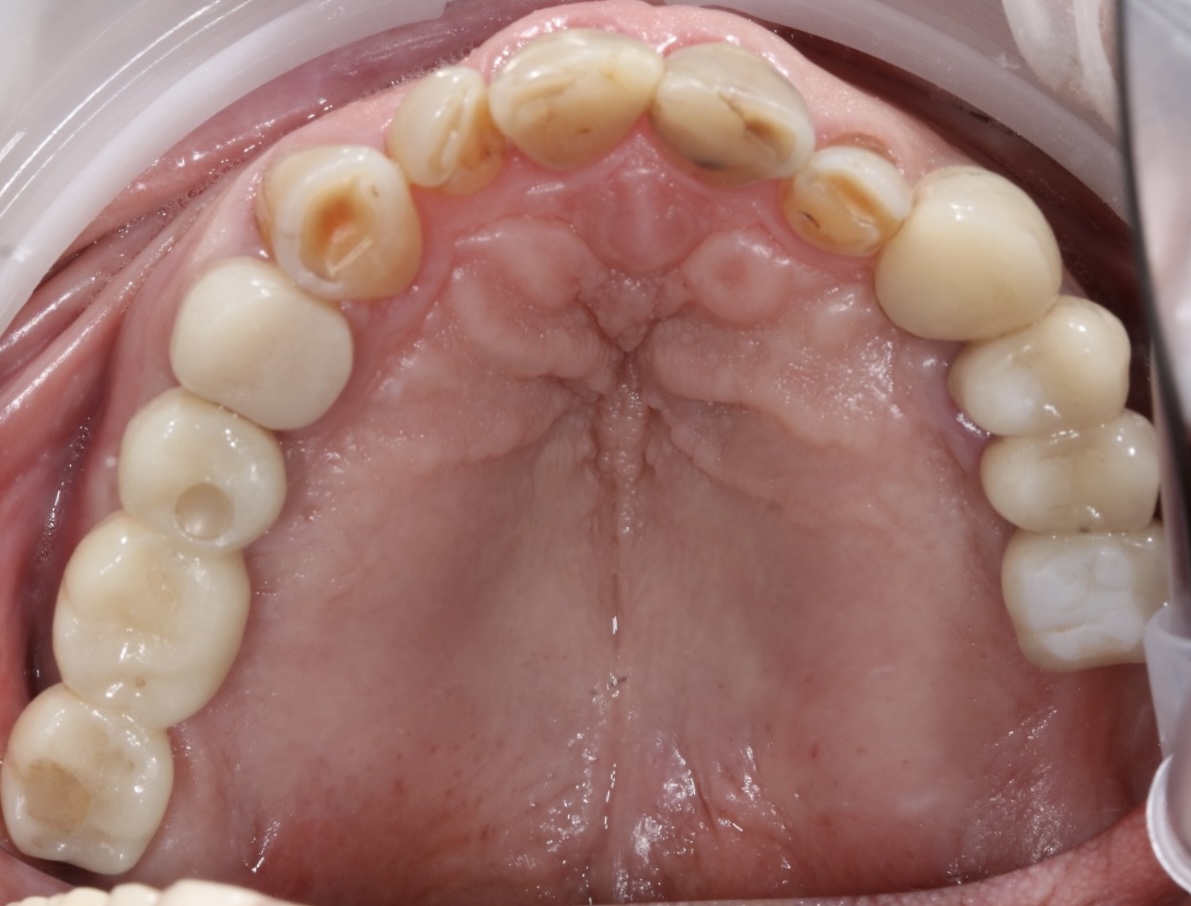

Implantati mogu da budu terapijsko rešenje u različitim situacijama - od nadoknađivanja pojedinačnih zuba u estetski najzahtevnijoj regiji kao što su prednji deo gornje vilice, preko nedostatka vićeg broja zuba pa do full mouth rekonstrukcija, gde se nadoknađuju puni zubni nizovi bilo u jednoj ili u obe vilice ALL-ON-4 ili ALL-ON-6 konceptom.

Nekada je ugradnja implanata jednostavna, a nekada je kompleksna i zahteva dodatne hiruške procedure različitog nivoa složenosti da bi se dobili optimalni uslovi za hirurgiju. Naš tim ima znanja, veštine i tehničke mogućnosti za izvođenje svih tih procedura gde se koriste zamenici za kost (“veštačka kost”), kost samog pacijenta, razne vrste membrana (veštačkih ili dobijenih iz krvi samog pacijenta), kao i primena faktora rasta izdvojenih iz krvi sve u cilju dobijanja najboljih uslova za ugradnju implanata i za kasnije protetsko zbrinjavanje kada se pacijent estetski i funkcionalno rehabilituje.